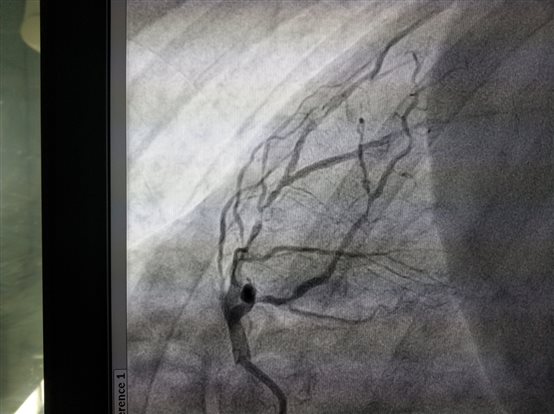

2018年7月4日上午中西医结合医院心内科又成功进行了一例冠脉支架植入术,此患者女性67岁,反复胸闷胸痛,活动后加重,冠脉造影提示前降支近中段严重狭窄95%,经介入治疗后前降支串联植入美敦力支架两枚,狭窄解除,血管通畅,患者症状解除,生活质量恢复。中西医结合医院心内科自2016年起即获得了上海市冠状动脉内治疗介入准入,有资质开展一系列治疗。并且上海的医保覆盖患者可以享受和其他医院一样的优惠支付政策。